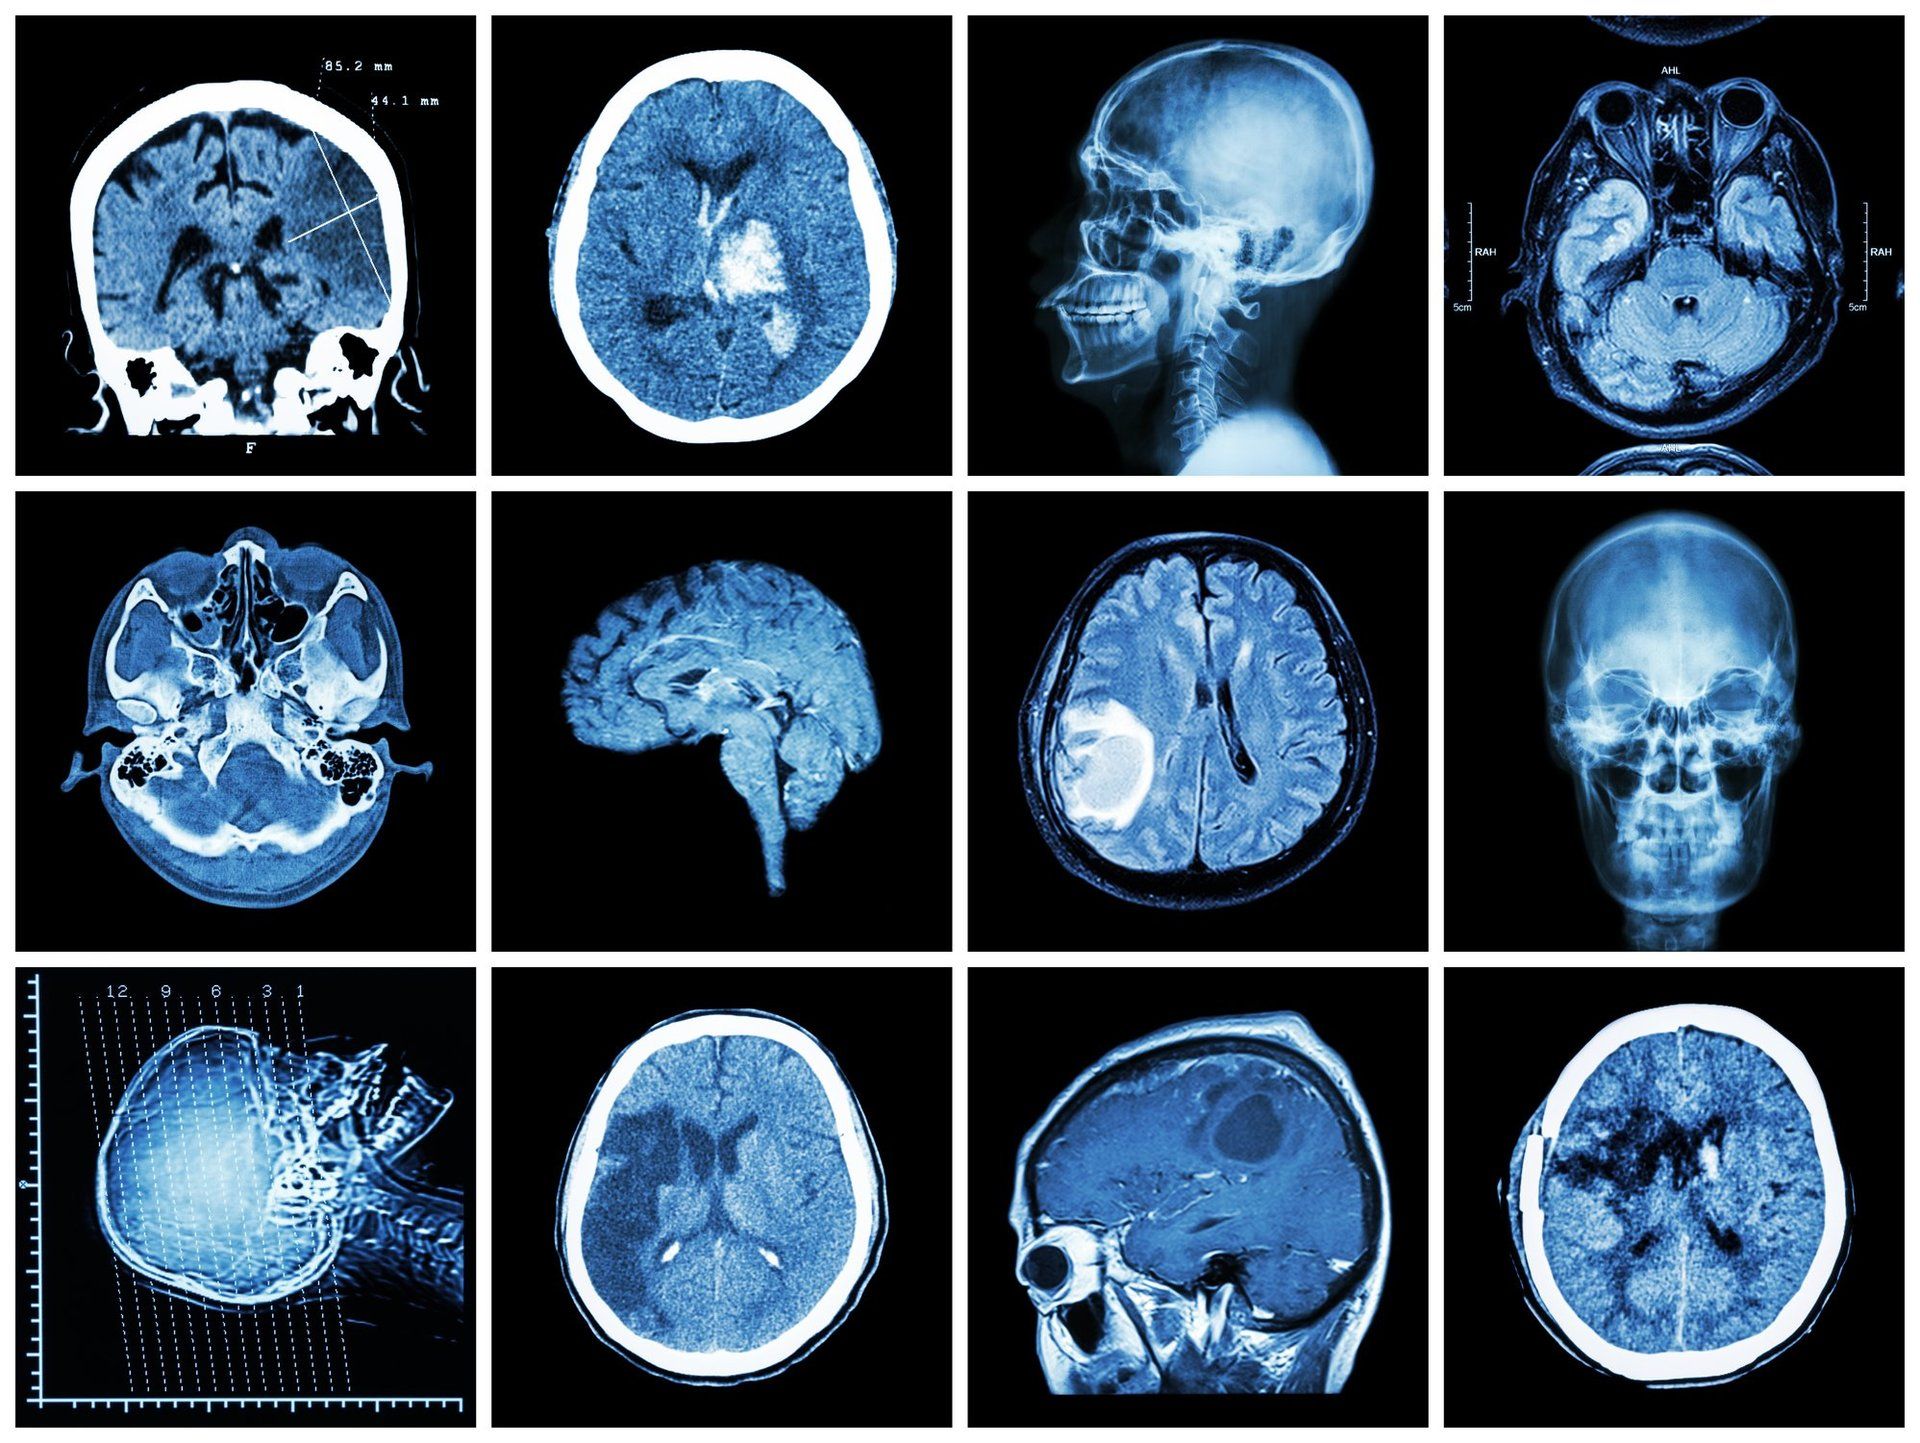

Subjects underwent an MRI to measure the volume of their brain. What they found was a dramatic reduction in the amount of white matter in overweight subjects. The white matter connects areas of the brain and allows information to be communicated between regions.